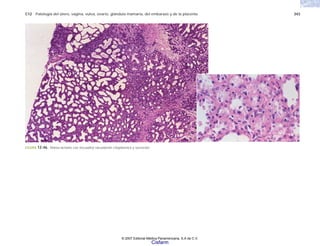

FIGURA 2-5. Histología de la piel en la esclerodermia, con abundante colágena por debajo del nivel de

las glándulas sudoríparas.